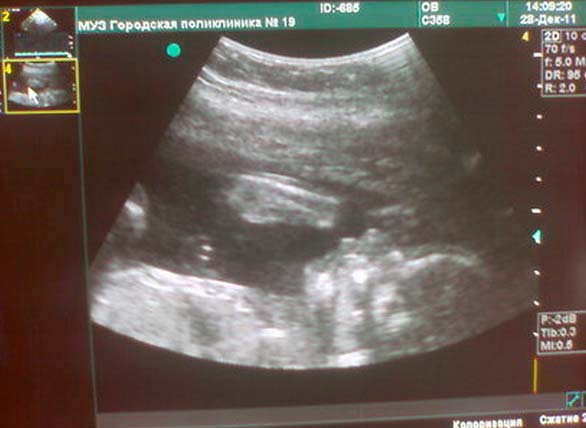

Foto de ultrassom na semana 22